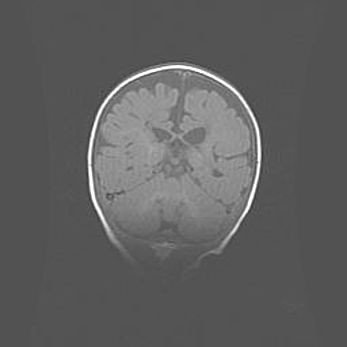

Лейкомаляция с кистозно-глиозной дегенерацией головного мозга.

Возраст: 2 месяца 25 дней

Вес: 6400 г

Окружность головы: 40 см

Срок гестации: 41 неделя

Лейкомаляцию относят к ишемически-гипоксическим повреждениям головного мозга, диагностируемым у новорожденных. При лейкомаляции в головном мозге обнаруживают очаги некроза, возникшие после тяжелой гипоксии и нарушения кровотока. В процессе морфогенеза очаги проходят три стадии: 1) развития некроза, 2) резорбции и 3) формирования глиозного рубца или кисты. Перивентрикулярная лейкомаляция (ПЛ) встречается примерно в 12% случаев среди новорожденных, обычно – у недоношенных детей, причем, частота ее зависит от массы, с которой младенец появился на свет. Наибольшее число малышей страдает лейкомаляцией, если масса при рождении 1500-2500 г.